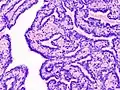

| Histopathology of intraductal papilloma of the breast by excisional biopsy. Immunostaining for p63 protein. | |

Histopathology of intraductal papilloma of the breast by excisional biopsy. Hematoxylin and eosin stain.